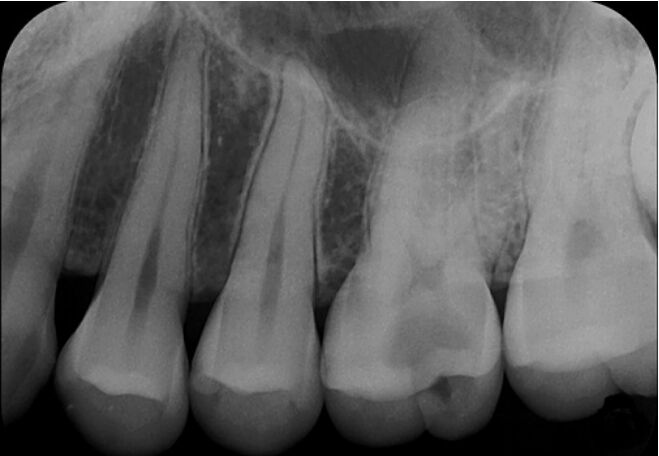

7.病人例行口腔檢查發現上顎左側第一大臼齒咬合面與遠心側有深部齲齒(deep caries),X光片如 圖所示,於探測時齲齒已深入牙髓腔。病人無自發性疼痛、冰與熱刺激皆有反應、無咬痛、敲診與觸診正常。針對上顎左側第一大臼齒的診斷何者正確? (A)牙髓診斷:可逆性牙髓炎(reversible pulpitis);牙根尖周圍診斷:正常根尖組織(normal apical tissue) (B)牙髓診斷:無症狀型不可逆性牙髓炎(asymptomatic irreversible pulpitis);牙根尖周圍診 斷:正常根尖組織(normal apical tissue) (C)牙髓診斷:無症狀型不可逆性牙髓炎(asymptomatic irreversible pulpitis);牙根尖周圍診 斷:無症狀型根尖周圍炎(asymptomatic apical periodontitis) (D)牙髓診斷:有症狀型不可逆性牙髓炎(symptomatic irreversible pulpitis);牙根尖周圍診 斷:無症狀型根尖周圍炎(asymptomatic apical periodontitis)